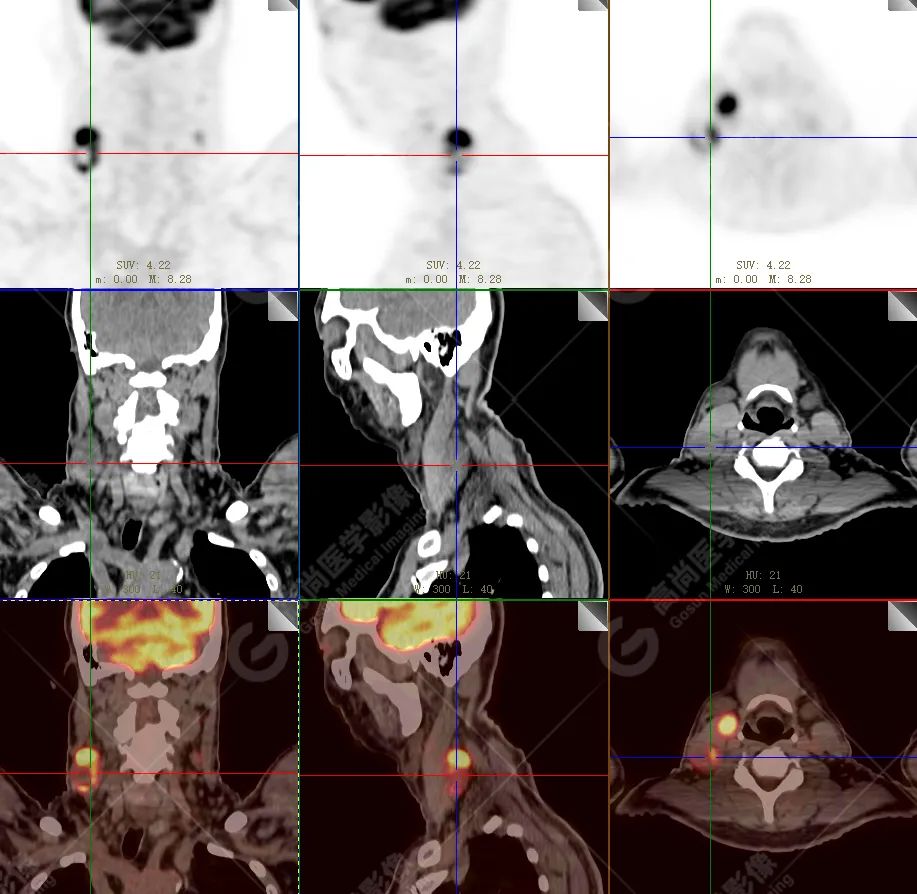

PET/CT 示:

上腭前部见一结节状放射性摄取增高影,大小约 1.6 cm×1.4 cm×1.0 cm,SUV 最大值为 10.5,CT 于上述部位见软组织密度影,边界不清,CT 值约 73 Hu(假牙金属伪影较多致 CT 值偏高)。右侧颈部(Ⅱ、Ⅲ区)及左侧颈部(Ⅰb、Ⅱ、Ⅲ区)见多发结节状及块状放射性摄取增高影,最大约 2.7 cm×2.6 cm×3.1 cm,部分放射性摄取增高,SUV 最大值为 17.7,部分病变内见放射性减低区,CT 于上述部位见增大淋巴结影。

PET/CT 结论:

1. 上腭前部结节状高代谢病灶,多考虑为恶性肿瘤(结合病史,较倾向于黑色素瘤),请结合病理学检查。

2. 右侧颈部(Ⅱ、Ⅲ区)及左侧颈部(Ⅰb、Ⅱ、Ⅲ区)多发淋巴结转移。

病理结果:

恶性黑色素瘤。